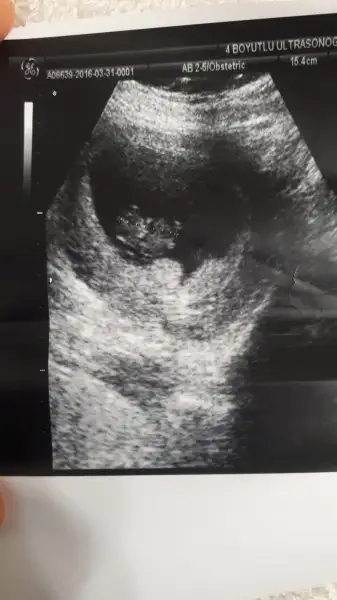

Karnımdan usg canım 7+2günlük..sağolasın merakla bekliyorımUsg karındansa erkek gibi,vajinalsa kız gibi cnm

bana yorum yok mu 9 haftalik karından usg

Havalianne__ Can'ım birsey danışmak istiyorum benim ilk usg 5+5 günlükken ondan Bebek solda ( yani vajinal bakılmıştı ve sağdaydı ) erkek olabilir dediniz şimdi Bebek 8+3 olmuş bugun ve karıbdab usg ile sağda yani buna göre kız ihtimali yüksek sence hangi haftayı dikkate almalıyım çok teşekkürler şimdiden